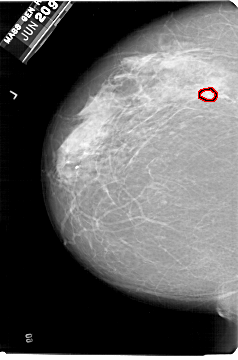

A_1329_1.LEFT_MLO

FILE: A_1329_1.LEFT_MLO.OVERLAY

TOTAL_ABNORMALITIES 1

ABNORMALITY 1

LESION_TYPE MASS SHAPE OVAL MARGINS ILL_DEFINED

ASSESSMENT 4

SUBTLETY 2

PATHOLOGY MALIGNANT

TOTAL_OUTLINES 1

BOUNDARY